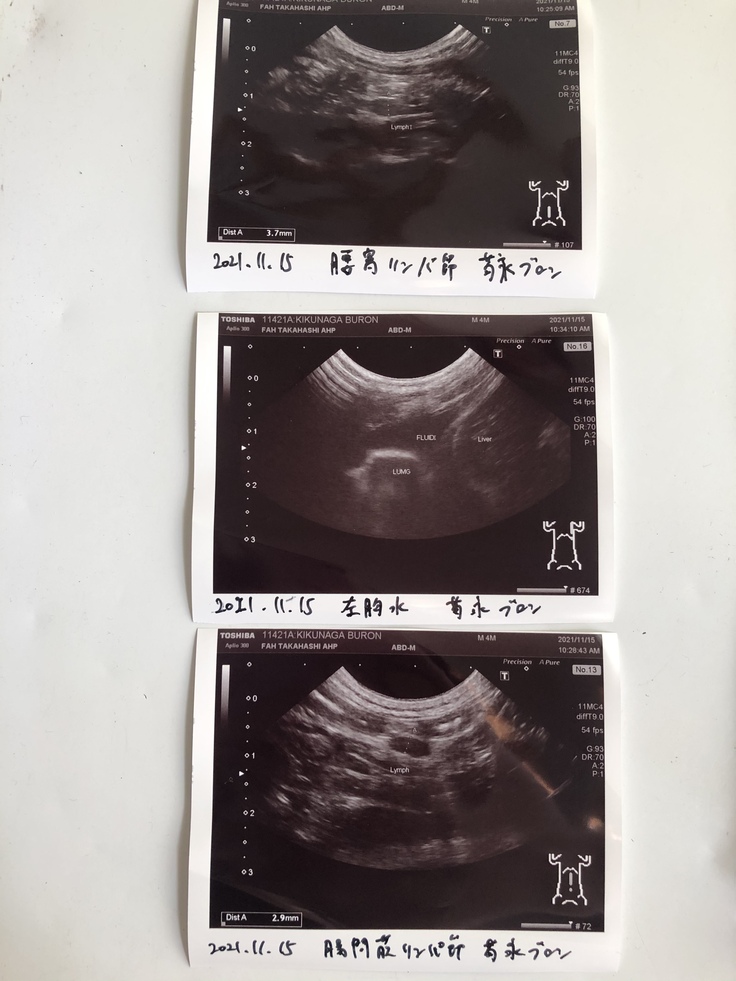

胸水もかなり貯留してしたため、200cc抜去しました。胸水のPCR検査、血液検査とエコーの結果、FIPウエットタイプ初期と診断されました。

エコー検査(1ヶ月おき)